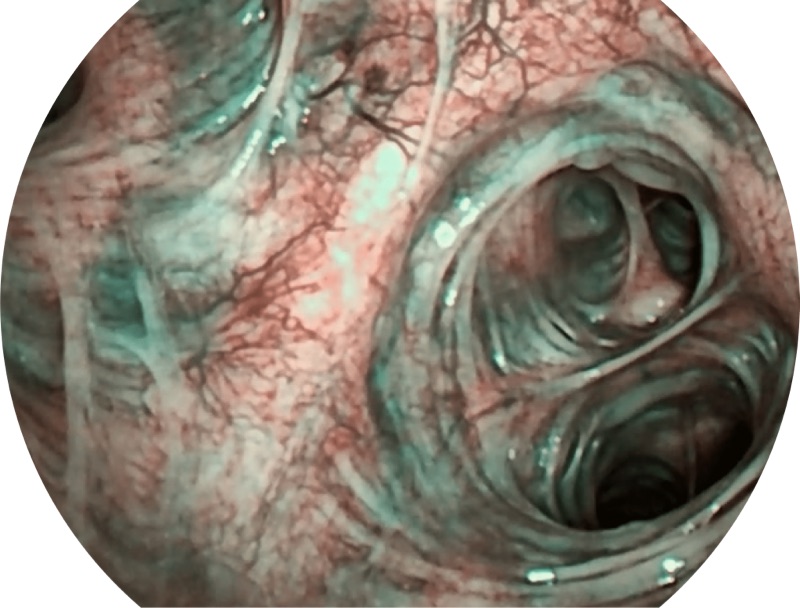

• SFI

• VIST